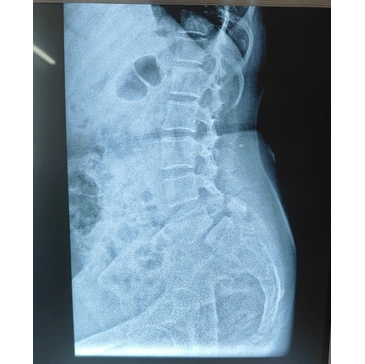

• Imaging tests to identify affected spinal area

• Diagnostic imaging to evaluate spine condition

How do doctors diagnose spine problems before recommending surgery?

Diagnosis typically includes clinical examination and imaging such as X-ray, MRI, or CT scan.